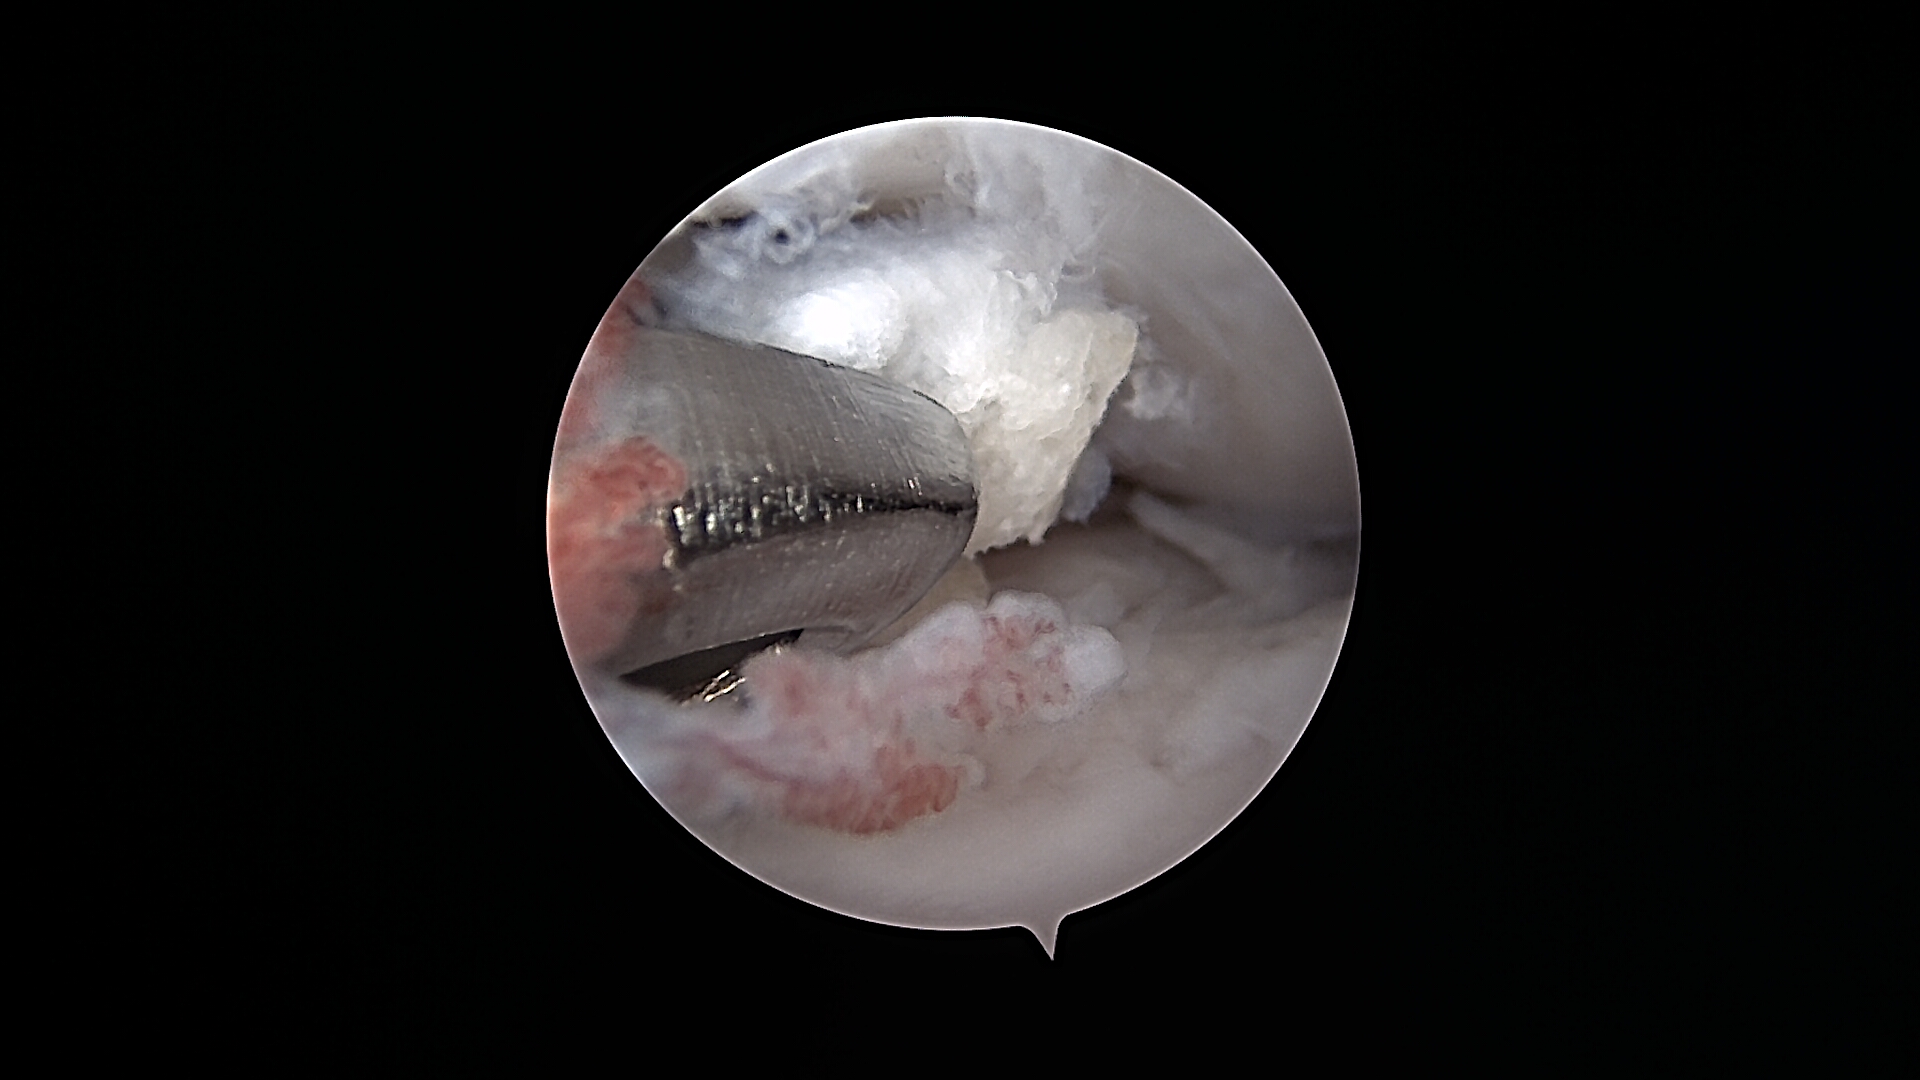

L’arthroscopie permet de diagnostiquer avec précision et de traiter différentes composantes de la dysplasie du coude, en particulier la fragmentation du processus coronoïde médial de l’ulna, qui est l’une des lésions les plus fréquentes. Elle permet également d’explorer et de traiter les lésions cartilagineuses associées, les remaniements de l’os sous-chondral, ainsi que certaines formes d’ostéochondrite disséquante du condyle huméral médial.

Grâce à l’arthroscopie, les lésions peuvent être visualisées directement, fragmentées ou retirées de manière ciblée, tout en limitant l’agression de l’articulation. Cette approche favorise une récupération fonctionnelle plus rapide et permet d’adapter au mieux la prise en charge globale, notamment en association avec d’autres techniques chirurgicales lorsque cela est nécessaire.

De gauche à droite : Retrait d’un fragment de processus coronoïde interne sur le coude d’un Cane Corso. Volet d’OCD sur une épaule d’un Border Collie. Exploration du genou d’un Berger Australien : LCP = ligament croisé postérieur, LCA = ligament croisé antérieur.